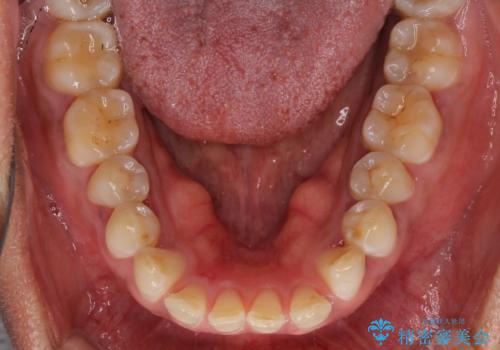

反対咬合の改善 途中で出産をしながらワイヤー矯正

- 矯正装置

- メタルブラケット

- 前歯の隙間と反対咬合を気にして来院された患者様です。

マウスピース矯正も提案しましたが、しっかりと使用する自信がないとのことで、ワイヤー装置により矯正治療を行うこととしました。

咬合力が強く、反対咬合の改善に時間がかかりましたが、その後はスムーズに進めることができました。

途中、妊娠と出産があり、治療が中断したため、治療期間は延びましたが、出産も矯正治療も無事に終えることができました。